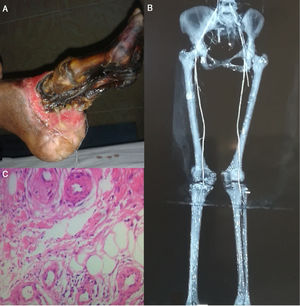

Case reportA 28 years old woman presented to our hospital because of progressive painful blackish discoloration of her left foot which started from the big toe and progressed up to the heel over a 4 months period (Fig. 1A) and was associated with intermittent claudication, on and off low-grade fever, blackening of the right first, second and third toe almost one month later,diffuse abdominal pain poorly relieved with medication and a weight loss of six kilograms during this period. The patient did not have any history of smoking, allergies, Raynaud's phenomenon or any similar complaints neither in the past nor anyone had them in the family. The patient had received anti-coagulants from local hospital but no beneficial effects were achieved. Pulse was regular, symmetrical and comparable in the upper limbs but absent in the lower limbs. In the left foot there were necrotic changes (dry gangrene) up to heel and in the right foot first three toes were involved up to MP joints. Rest of the examination was unremarkable. CBC showed Hb 9.8g/dL, WBC 13,200/uL, platelets 232,000/uL. Erythrocyte sedimentation rate was 44mm/h. Creatinine was 1.9mg/dL and urea was 48mg/dL. Liver function tests were within normal range. Alkaline phosphatase was 860U/L. HbsAg and anti-HCV were negative. Anti-Nuclear antibodies, anti-Cardiolipin antibodies IgM and IgG were normal (0.49, 4.36 and 5.26U/ml respectively). CXR, echocardiography and abdominal ultrasound were unremarkable. CT angiography showed multiple filling defects in the segmental branches of left renal artery with small left kidney, a filling defect in the distal 6cm of abdominal aorta extending upto both common iliac arteries and collateral flow was seen from superior mesenteric artery to external iliac artery. Filling defects were seen in left tibio peroneal trunk and in right distal femoral artery along with gradual attenuation of right anterior tibialis artery and absent dorsalis pedis (Fig. 1B). Diagnosis of PAN was made on the tissue diagnosis taken from the involved skin (Fig. 1C). The patient received iv steroids which improved the symptoms and halted the disease process but transmetatarsal amputation of left foot was done as dry gangrene converted into wet gangrene. At 6 months follow up the gangrenous changes in the right foot were conserved and patient had no symptoms of the active disease.